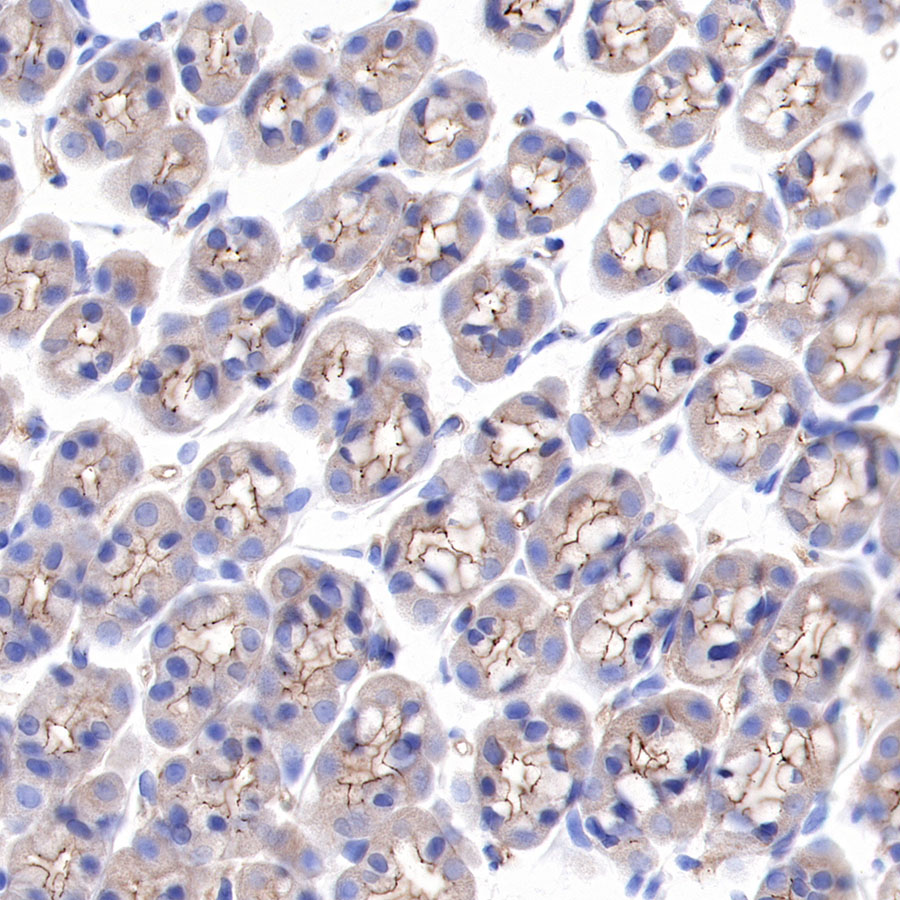

IHC shows positive staining in paraffin-embedded rat kidney. Anti-α-Actinin-1 antibody was used at 1/2000 dilution, followed by a HRP Polymer for Mouse & Rabbit IgG (ready to use). Counterstained with hematoxylin. Heat mediated antigen retrieval with Tris/EDTA buffer pH9.0 was performed before commencing with IHC staining protocol.